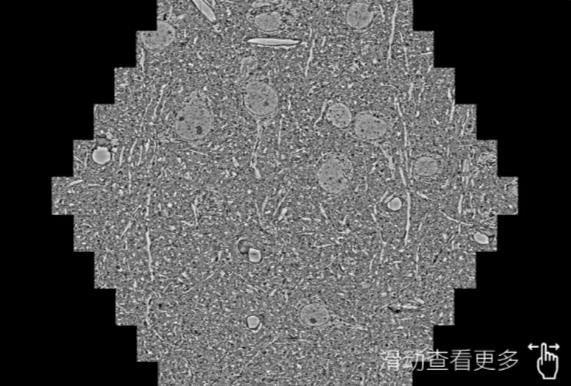

鼠脑切片。左图使用福州蔡司福州扫描电镜MultiSEM706对165μmx143pm面积区域成像,耗时仅需1.5秒。右图为鼠脑切片中30μm区域放大效果。样品由芝加哥大学B.Kasthuri提供。

使用蔡司高速福州扫描电镜MultiSEM对1mm²人脑皮层组织进行高分辨成像,并对其中的各种细胞结构进行三维重构分析。左图展示了2x3mm²组织平面中锥体神经元的三维重构效果。右图显示了局部体积神经元三维重构。图像由哈佛大学chtman实验室提供,渲染图由D. Berger 制作。